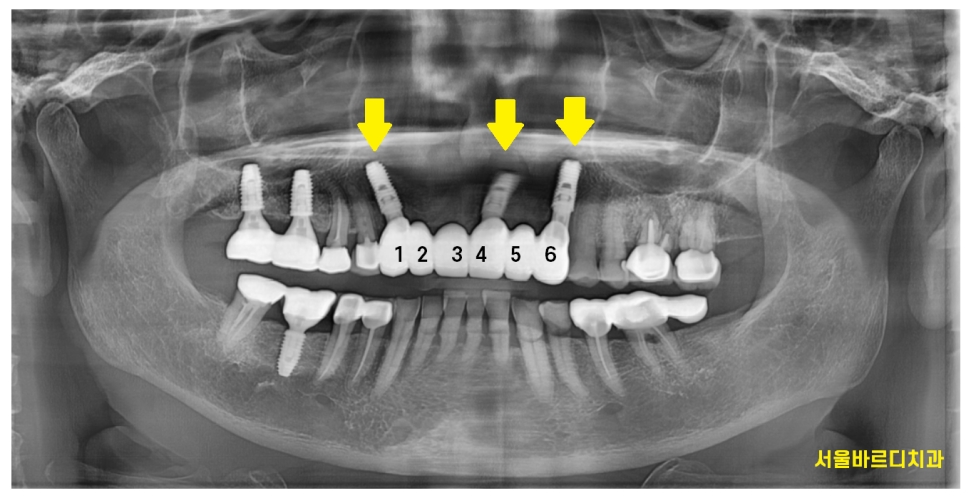

24.07.31

6개의 앞니 임플란트 브릿지로 완성해드렸습니다.

자연치 상태에서는 4개 치아가 6개의 치아 힘을 분산했는데

앞니 브릿지 교체하면서

임플란트는 3개만 심어드렸습니다.

1개의 비용을 덜어드린 셈이죠.

1개 가격도 무시 못합니다~~